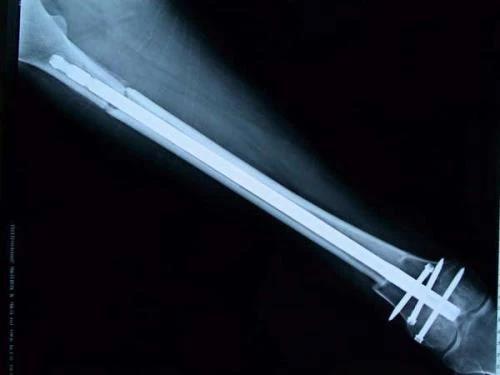

保肢治療指經(jīng)典型骨肉瘤在多學科團隊醫(yī)生共同努力下完成的新輔助化療、保肢手術(shù)和輔助化療等一系列治療總稱,其目的是在提高患者生存率的前提下,減少局部復發(fā)、盡量保留良好的肢體功能。肢體經(jīng)典型骨肉瘤保肢治療方法如下圖所示: